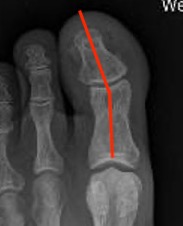

Weight Bearing AP X-ray

Angles

| HVA | DMAA | IMA | HVI |

|---|---|---|---|

|

HVA - hallux valgus angle - metatarsophalangeal angle (MTPA)

Normal < 15o |

Distal metatarsal articular angle

Intermetatarsal angle

Normal < 9o |

Hallux valgus interphalangeus

Normal <10o |